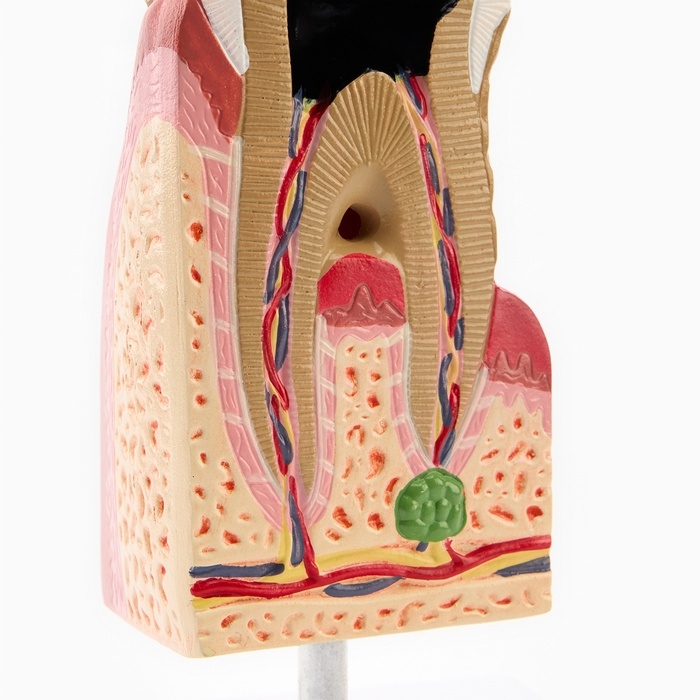

ЕКБ 93

No Brand, артикул: 7072363